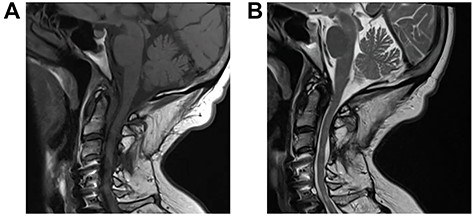

A 64-year-old female status post-two prior spine surgeries presented with recurrent cervical myelopathy. Magnetic resonance imaging (MRI) revealed a 1-cm ventral medullary cyst (Fig. 1A–D), which had enlarged compared with prior imaging. There was significant C1-2 joint arthropathy but no overt instability. She underwent uncomplicated left minimal access far-lateral transcondylar craniotomy for cyst resection. The cyst contained viscous material and was sharply resected, with the exception of the dorsal wall densely adherent to the brainstem. Pathology specimens revealed benign fibroconnective tissue with fibrinous degeneration and focal vascular proliferation (Fig. 2A and B). Immunohistochemical staining for S-100, glial fibrillary acidic protein (GFAP), progesterone receptor (PR), epithelial membrane antigen (EMA) and carcinoembryonic antigen (CEA) was negative; these findings were consistent with a ganglion cyst. Her pain resolved and strength and balance improved post-operatively. Repeat imaging 4 months post-operation demonstrated gross total cyst resection with resolution of the bulbar syrinx and reconstitution of appropriate ventral medullary anatomy (Fig. 3A and B).

Repeat MRI 4 months post-minimal access far-lateral transcondylar approach for resection of the C1-2 degenerative cyst; sagittal T1-weighted (A) and T2-weighted (B) sequences demonstrate gross total resection of the cyst with complete resolution of the medullary syrinx.